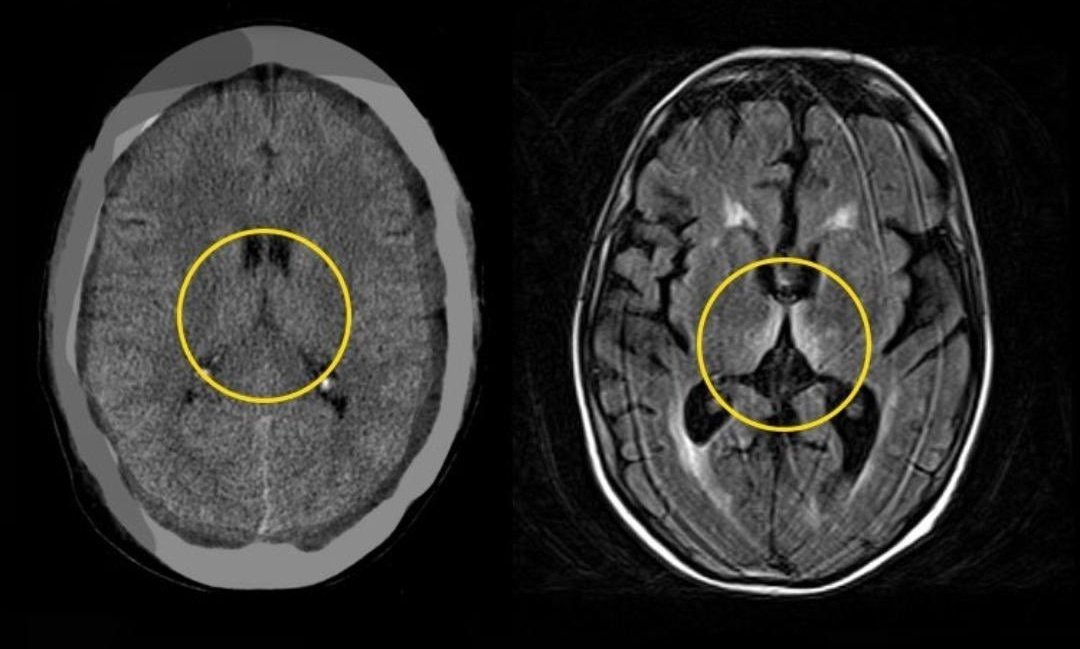

🔸نقصه يؤدي الى ⬅️ فقر الدم الضخم ْ وإعتلال الأعصاب الطرفية والتأثير على الحبل الشوكي ⬅️

Subacute Combined Degeneration of spinal cord